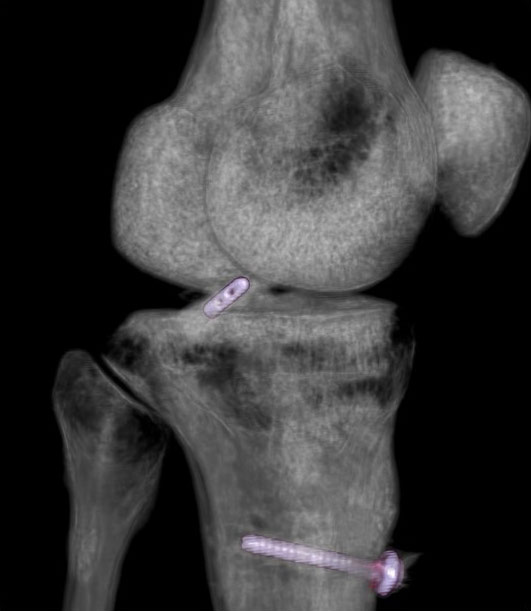

Reconstrucții cu parametri speciali

Imaginile cu parametri de os (“kernel” dedicat osului) sunt cu conturi mult mai netede, mai exacte, mai “sharp”, care permite o foarte bună apreciere a celor mai fine traiecte de fractură, însă imaginile 3D obținute pe seama acestora nu sunt la fel utile, fiind cu margini ascuțite și un aspect mai puțin plăcut vizual datorită prea multor detalii prezente.

Reconstrucții tridimensionale